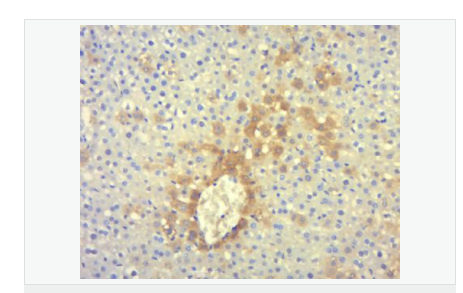

| 產(chǎn)品應(yīng)用 | ELISA=1:5000-10000 IHC-P=1:100-500 IHC-F=1:100-500 Flow-Cyt=1ug/Test IF=1:100-500 (石蠟切片需做抗原修復(fù)) not yet tested in other applications. optimal dilutions/concentrations should be determined by the end user. |

| 細胞定位 | 細胞漿 |